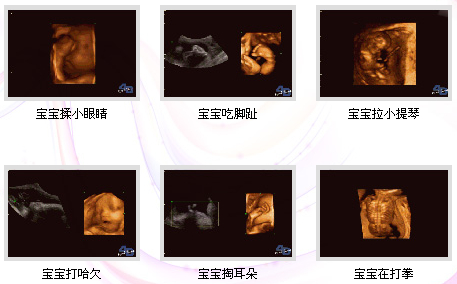

四維彩超簡(jiǎn)稱"4D",也就是四維成像技術(shù),是目前上較為先進(jìn)的超聲診斷技術(shù),能直觀、立體顯示人體器官的三維結(jié)構(gòu)及動(dòng)態(tài)、實(shí)時(shí)地觀察立體結(jié)構(gòu),廣泛運(yùn)用于對(duì)胎兒進(jìn)行超聲檢查,立體觀察宮內(nèi)胎兒發(fā)育情況的同時(shí),還能清晰顯示胎兒在宮內(nèi)的動(dòng)態(tài),讓準(zhǔn)爸爸準(zhǔn)媽媽一起觀看寶寶在媽媽肚子里的各種動(dòng)作神態(tài),另外還能制作成光盤,讓寶寶擁有較完整的0歲相冊(cè),留下的記憶。 >>>>看文章太累?直接聯(lián)系在線產(chǎn)科醫(yī)生

作為準(zhǔn)媽媽的你,擁有一個(gè)健康的寶寶是你的要求。莆田盛興醫(yī)院引進(jìn)的美囯GE四維彩超設(shè)備,就是為了準(zhǔn)媽媽擁有健康的寶寶而提供的科學(xué)保障。準(zhǔn)媽媽們通過(guò)四維彩超,不僅可以看到宮內(nèi)胎兒打哈欠、伸懶腰、吮手指等等好看的動(dòng)作,還能夠多方位、多角度觀察宮內(nèi)胎兒的生長(zhǎng)發(fā)育情況,為早期診斷胎兒先天性體表畸形、先天性心臟疾病提供準(zhǔn)確的科學(xué)依據(jù),并可以直觀的觀測(cè)胎兒實(shí)時(shí)動(dòng)態(tài)活動(dòng)圖像。

四維彩超視頻是什么樣子的?

莆田盛興醫(yī)院產(chǎn)科醫(yī)生:四維彩超能多方位、多角度地觀察宮內(nèi)胎兒的生長(zhǎng)發(fā)育情況,為早期診斷胎兒先天性體表畸形和先天性心臟疾病提供準(zhǔn)確的科學(xué)依據(jù)。四維彩超圖像清晰,可將寶寶的樣子和動(dòng)作制作成照片或DVD,讓寶寶擁有較完整的0歲寫真。